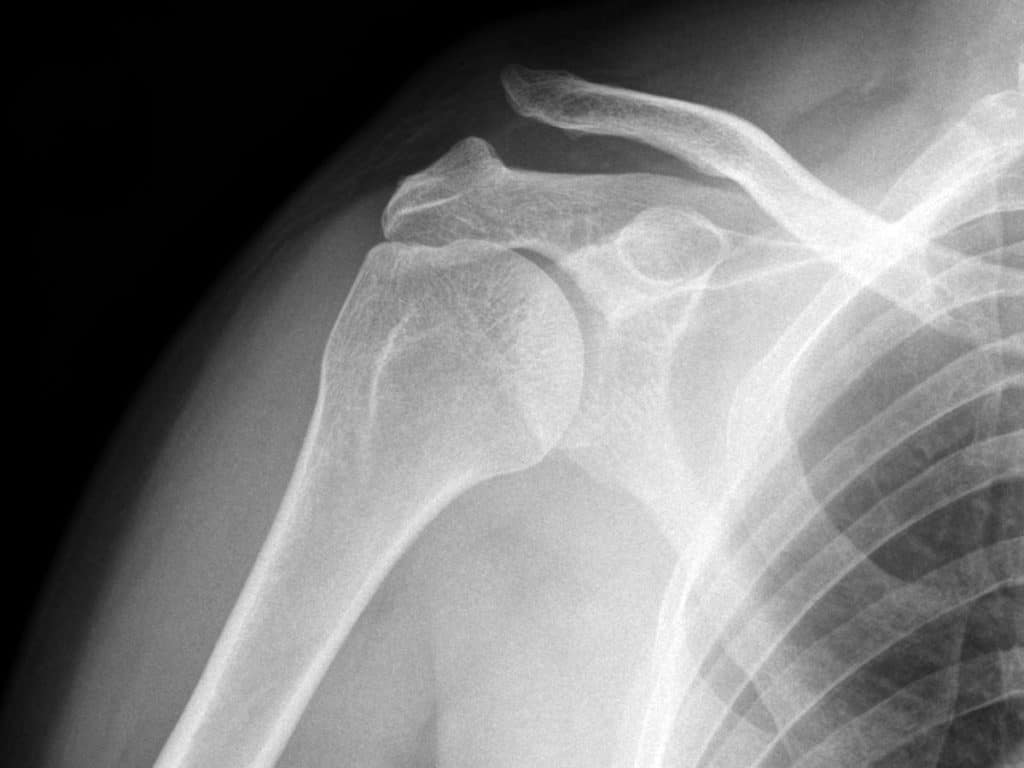

Рентгенография акромиально-ключичных суставов. Вывих акромиального конца левой ключицы (справа норма для сравнения).

• Рентгенологическое исследование. Для подтверждения выполняют снимок акромиально-ключичного сустава или рентгенографию грудино-ключичного сочленения. При неполных вывихах ключицы в некоторых случаях требуется сравнительная рентгенограмма обеих сочленений, иногда — с функциональной нагрузкой (пациент берет в руки небольшой груз).

Диагноз вывиха акромиального конца ключицы иногда очень прост и все очевидно при осмотре, а иногда приходится решать целую головоломку. Наиболее оптимальным и распространенным способом диагностики является рентгенография. Стоит сказать, что, как не бывает одинаковых людей, так и не бывает одинаковых ключиц. Чаще всего причиной ложного диагноза индивидуальные особенности акромиально-ключичного сустава.

Поэтому целесообразно выполнять рентгенограмму не одного плеча, а двух сразу — что позволит оценить нормальное строение противоположной ключицы.

В сомнительных случаях иногда выполняют функциональную рентгенографию — в руку берут груз, который оттягивает ее вниз и вывих становится более очевидным.